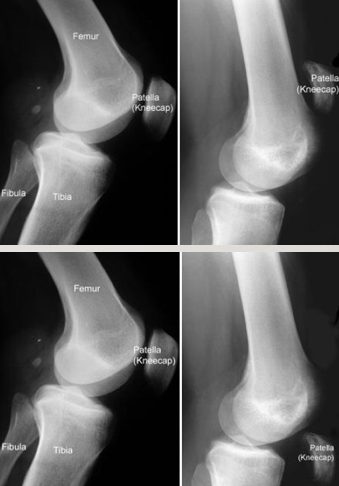

Knee: Bipartite Patella

Etiology: lack of fusion of patella at growth area; results in patella that is in multiple pieces

Typically, only hurts if there is repetitive trauma but patient cannot recall a specific injury

Incidental finding on radiograph

Common symptoms/ complaints:

Typically, asymptomatic

Sometimes pain resulting from trauma

Physical Exam:

TTP over patella if inflamed; otherwise, unremarkable

Tests:

X-rays: edges will often not be as sharp as fractures

MRI can help to visualize inflammation